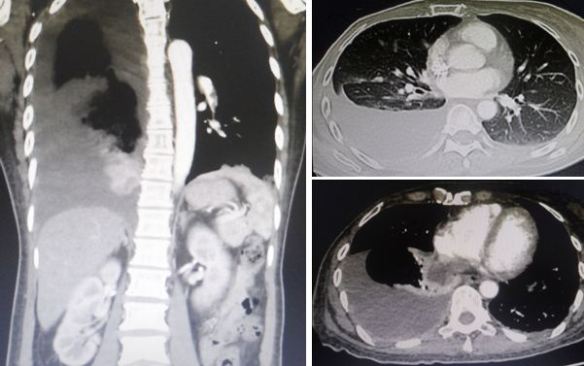

ST is a 62-year-old man from Perak. Two years ago (May 2018) he was diagnosed with cancer of the appendix and adjacent caecum.

A CT scan of the chest, abdomen and pelvis did not show the cancer had spread to other parts of the body.

In March 2020, ST started to have abdominal pain and at times, he vomited. He went back to the same hospital where he had his surgery. A CT scan was done and revealed:

• Acute small bowel obstruction with no evidence of tumour recurrence.

• Liver lesions – cyst or metastasis ?

• Bilateral small renal cyst.

A CT scan done on 4 August 2020 showed:

• Progression of disease evidenced by increased number and size of cystic liver lesions – likely metastasis.

• No evidence of recurrence.

• Prostatomegaly.